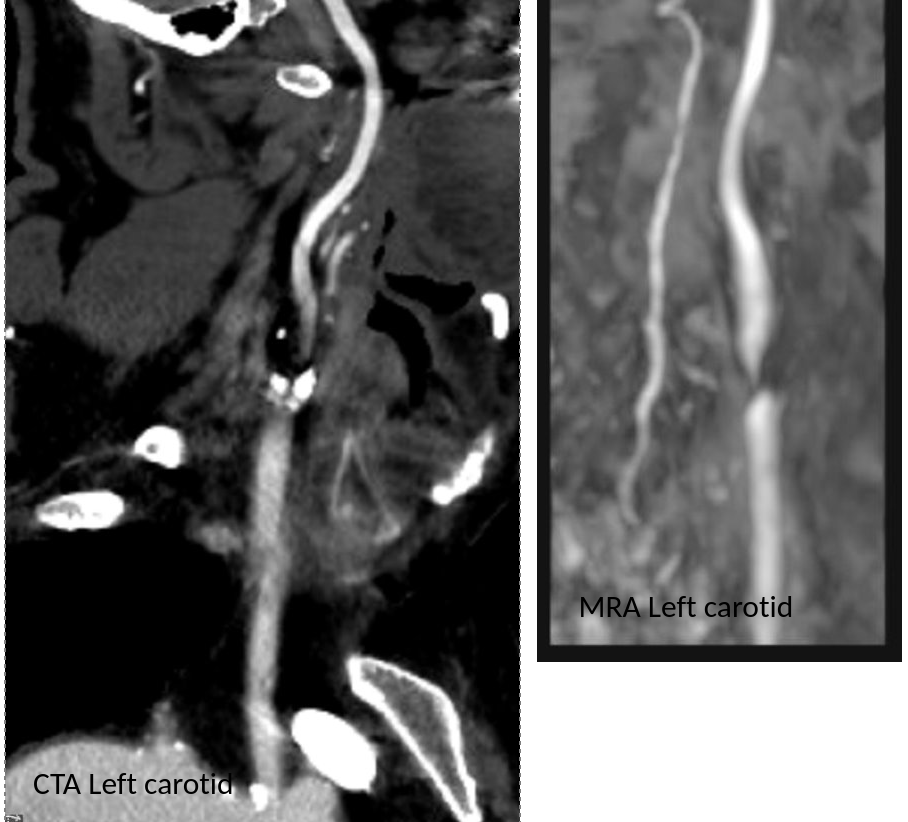

The patient is a man in his 80’s who presented with left sided weakness and dysarthria. Over 25 years before, he had undergone a carotid endarterectomy after a stroke, and had remained stroke free since. Per protocol, he received systemic thrombolysis and underwent CT angiography which revealed a right sided patch pseudoaneurysm.

He stabilized and regained much of his function on the left arm and leg, while having a residual paresthesia of the left leg. His dysarthria resolved. His left carotid system was affected by a severe stenosis confirmed on MRA.

Duplex confirmed a tight stenosis of the left ICA with biphasic flows in the ECA.